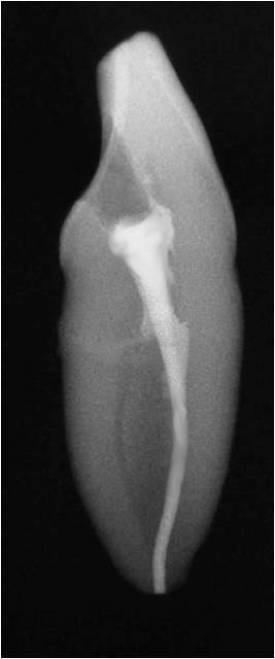

Fig 13. A good root canal may have been absorbed.

Figure 13

Figure 13 shows an example where there was likely a good root canal that was absorbed. The way to avoid this type of problem is that the person who does the root canal should do the post. This is not always possible, and some general dentists like to do the restorative work themselves, but the advantage of having the same person do both is that the person is familiar with the curve of that canal. That clinician also knows the thickness of the walls and what the canal will allow. In this case, it was done under a rubber dam, which was beneficial; often clinicians will see teeth that have good endodontics, but multiple years later, radiolucency will appear because when the post was placed, saliva seeped in.